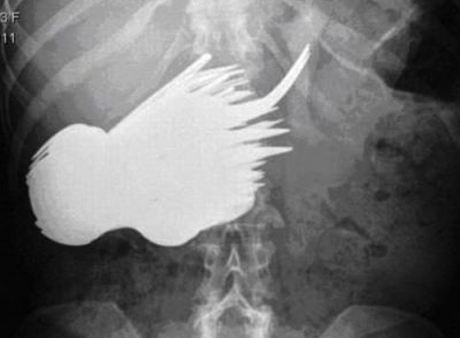

یک زن 52 ساله آلمانی با نام “مارگارت دالمن” پس از احساس درد شدید از ناحیه شکم به بیمارستان مراجعه می کند ، پزشکها بعد از گرفتن عکس اشعه ایکس از این زن با صحنه وحشتناک و نادری روبرو شدند.

به گزارش ایران ناز دکترها پس از دیدن این اشیاء در درون شکم وی را به سرعت به اتاق عمل انتقال دادند پس از جراجی وی 72 عدد قاشق و چنگال در شکم او پیدا و خارج کردند. اینکه چگونه این تعداد قاشق و چنگال به معده این زن 52 ساله راه پیدا کرده بعنوان راز پا برجاست.